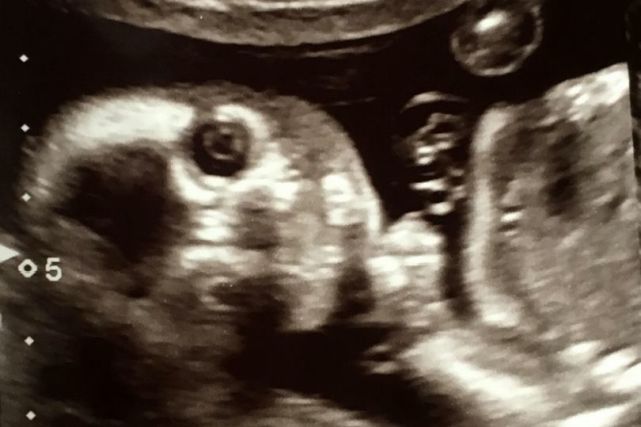

2月13日,英国《太阳报》登载了一张可爱的B超照片,照片中,小胎儿居然直视镜头,看起来像个小鬼般精灵可爱。

格里尔也是一位准妈妈,在做孕20周例行检查时,医生为胎儿做了B超扫描。

不过做B超时,医生和格里尔都吃了一惊,因为格里尔腹中的小宝宝突然转了一个位置,目光直视镜头,看起来很机灵、别具神采。医生说这样的情形是很罕见的。